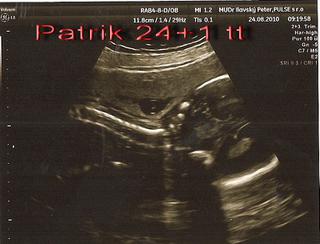

Ahojte, hlásim sa z poradne, dnes bol odber na tú tehotenskú cukrovku, + ster z krčka. Zatiaľ to vyzerá stále na cisársky kvôli placente, mám ju v predu dolný segment a praevia centralis - čiže bráni normálnemu pôrodu. A preto mám aj menšie bruško ako by malo na 7 mesiac byť. Uvidíme, možno sa to ešte zmení, ale hlavne že malý je v poriadku, i keď dnes moc nespolupracoval krpček jeden.

Prikladám dnešné foto, no zke to je rozoznať, je tam hlavička, noštek, pusinka a chrbátik.